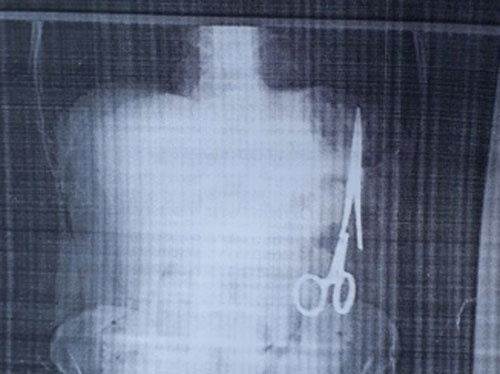

Sau khi kiểm tra, các chuyên gia xác nhận miếng gạc bị bỏ quên là nguyên nhân chính gây ra cái chết.

Băng gạc phẫu thuật là vật dụng phổ biến nhất thường bị bỏ quên trong cơ thể bệnh nhân khi phẫu thuật. Theo thống kê thực tế của một nghiên cứu năm 2007, khoảng 1.500 bệnh nhân bị bỏ quên vật dụng phẫu thuật, trong đó có tới 2/3 là băng gạc phẫu thuật.

Những miếng băng gạc là công cụ quan trọng trong phẫu thuật vì chúng giúp thấm máu và các chất dịch khác của cơ thể để giúp bác sĩ kiểm tra rõ ràng khu vực cần phẫu thuật. Ban đầu, chúng được đóng gói vô trùng, nhưng sau khi được sử dụng, chúng nhanh chóng trở thành nơi sản sinh màu mỡ cho mọi loại vi khuẩn.